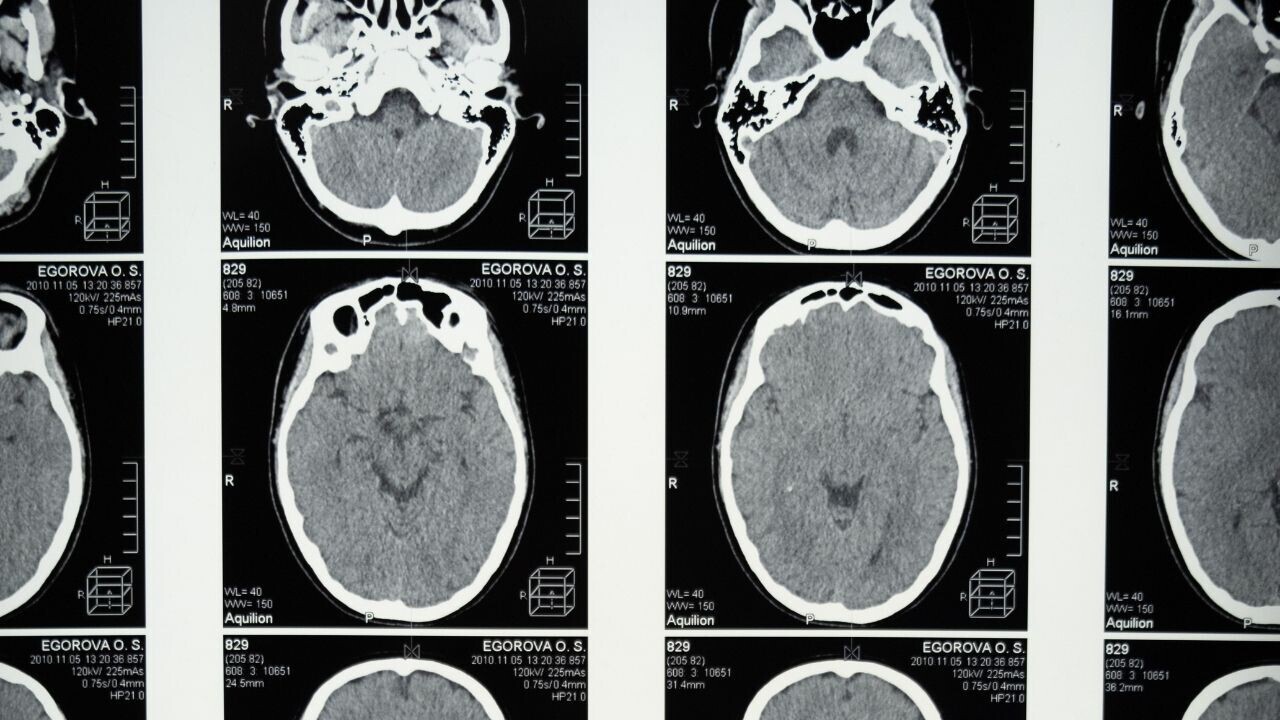

The system’s algorithm searches for patterns in brain scans that neurologists can’t detect. These are then matched to patient outcomes in a database to make a diagnosis.